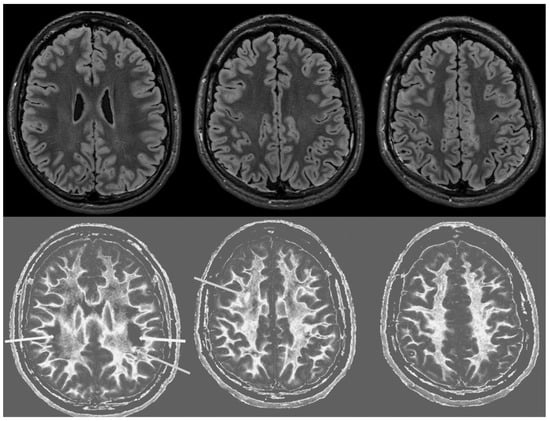

MRI findings:

Figure 6 and Figure 7 show T2-FLAIR images (upper rows) with positionally matched dSIR images (lower rows). No abnormalities are seen in the white matter on the T2-FLAIR images, but very extensive high signal abnormalities are seen in the white matter of the corresponding dSIR images. There is relative sparing of the anterior central corpus callosum and, to a lesser extent, the posterior central corpus callosum. There is also some sparing of the peripheral white matter in the cerebral hemispheres.

Overall, the MRI findings in Case 2 are very similar to those in Case 1, as shown in Figure 4 and Figure 5. They have been described as a whiteout sign. This often involves 80% or more of the white matter in the cerebral and cerebellar hemispheres having an abnormal high signal appearance.

Figure 6. Case 2 was examined two years after his asphyxial episode. Comparison of positionally matched T2-FLAIR images (upper row) and narrow mD dSIR images (lower row). No abnormality is seen on the T2-FLAIR images, but there are extensive areas of high signals in the white matter of the brain. The anterior and posterior central corpus callosum and parts of the frontal lobes have a lower, more normal signal (darker appearance). Horizontal CSF flow artefacts are seen in the dSIR image in the middle lower row.

Figure 7. Case 2 was examined two years after his asphyxial episode. Comparison of positionally matched T2-FLAIR images (upper row) and narrow mD dSIR images (lower row). No abnormality is seen on the T2-FLAIR images, but there are extensive areas of high signals in the central white matter of the brain (lower row). Only some of the peripheral white matter on the lower images appears darker and looks more normal on the dSIR images.